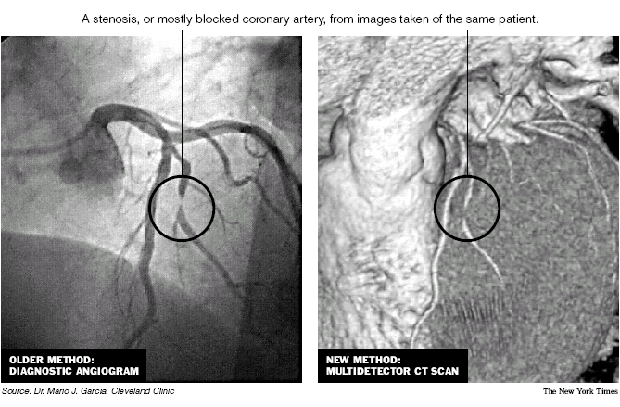

A fine pair of mapped pictures comparing image methods for coronary arteries. From the New York Times, November 17, 2004, p. A24. Original source: Dr. Mario J. Garcia, Cleveland Clinic.